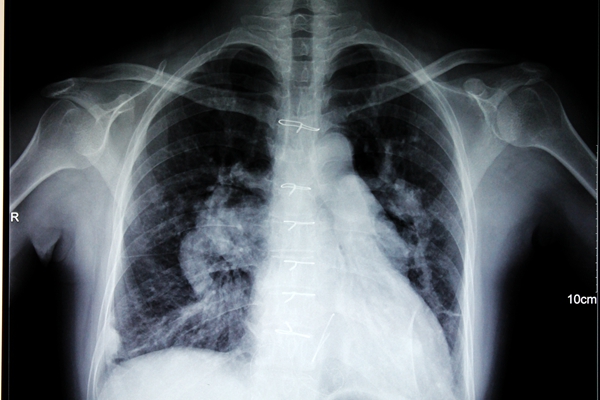

于是,12月底那场风险很大的手术中,杨柳山主任带领一支医技精湛的团队,沉着应对,为邓女士完成了房间隔缺损修补+三尖瓣成形的手术,除了三尖瓣成形这一手术中的精华部分,房间隔缺损修补还采取了活瓣修补的形式,以缓解右心房的压力。

邓女士手术后平安返回病房,顺利迎来了2014年新年元旦。